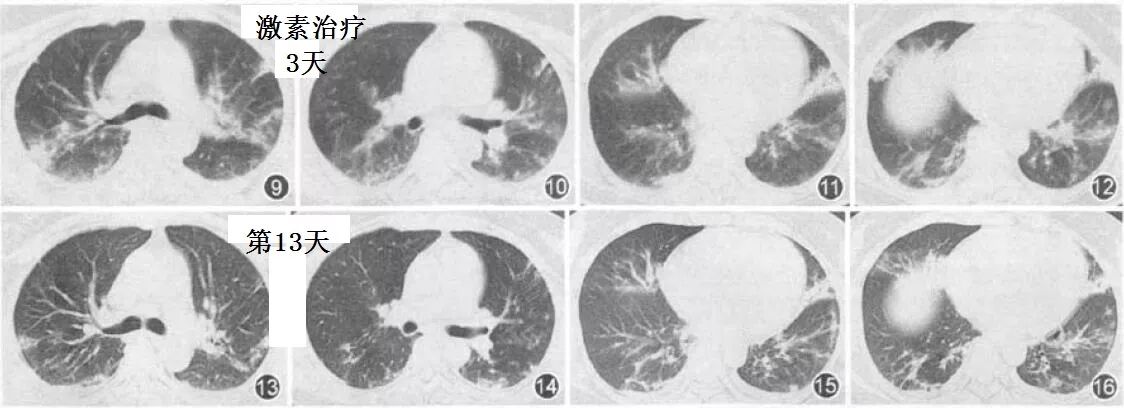

胸部CT,主要表现,还是双肺弥漫性分布的实变影及磨玻璃影。

病灶多,变化快,气难喘,斑片+磨玻璃。